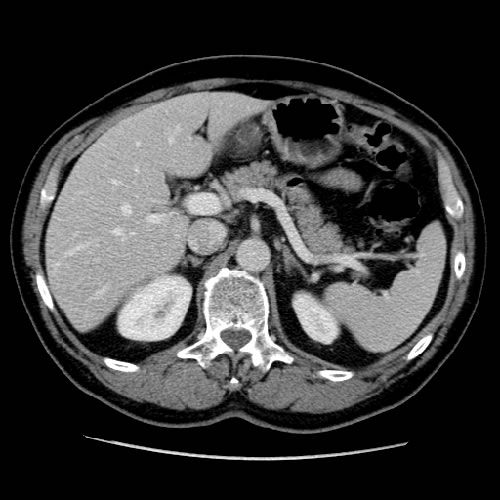

Il utilise les rayons X. C'est grâce à la rotation du système de détecteurs que le scanner permet la création d'images 2D et 3D, voire même 4D pour certains examens (scanner cardiaque).